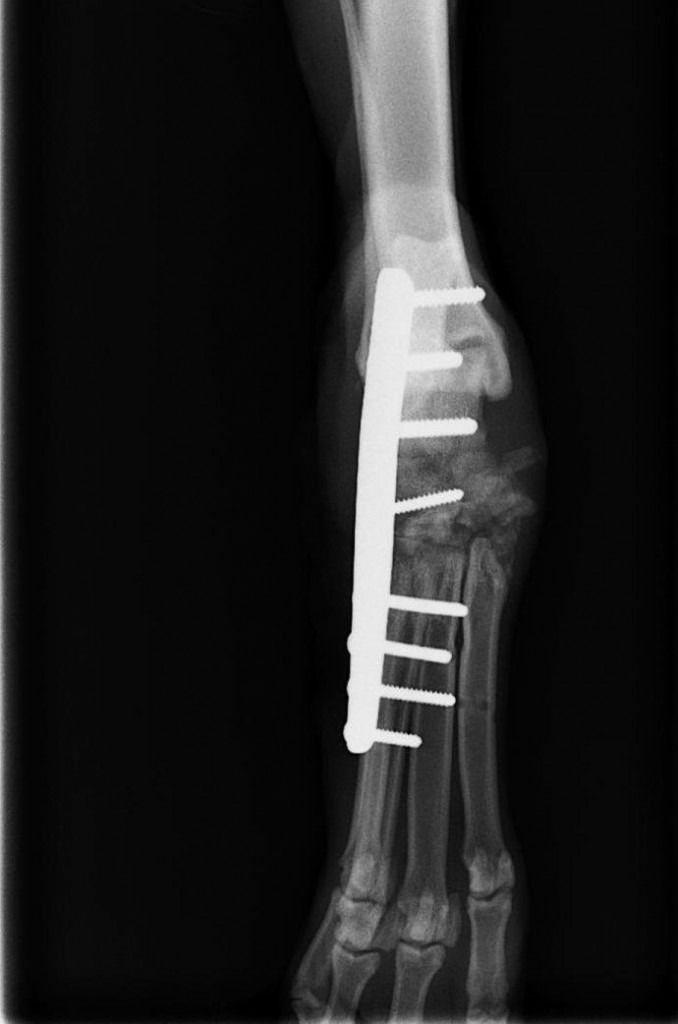

Fracturas

Es uno de los problemas más habituales en traumatología, las fracturas de huesos suelen ocurrir después de atropellos, caidas, disparos, golpes, etc.

La gran parte de la fracturas las resolvemos mediante la aplicación de fijación interna, y algunas con fijadores externos, dependiendo de las características de cada situación.

Las fracturas más frecuentes: mandíbula, húmero, cúbito y radio, cadera, fémur, tibia, metacarpianos.